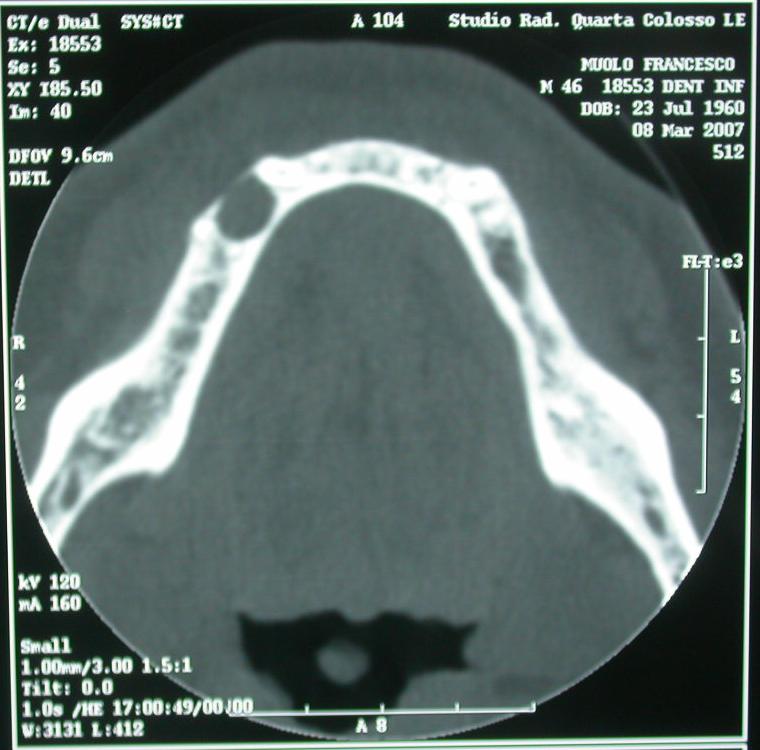

Dopo pochi mesi, nel luglio 2010, il paziente suo malgrado, è costretto a prendere per l’ennesima volta le dovute precauzioni, e recatosi d’urgenza all’Ospedale regionale nel reparto di Chirurgia Maxillo Facciale, dove emerge dall’esame clinico obbiettivo, essere affetto da una tumefazione cistica dell’emimandibola destra, con associata presenza di corpo metallico, si richiedeva TC dentascan mandibolare; (foto 7-8)

foto 7 – 8 tc dentascan

dal referto della Tc Dentascan della mandibola emerge:

Granuloma apicale del 45 che si estende nella regione

del 44,

(ove si apprezzano residui dentari);

Corpo estraneo a densità metallica si apprezza nei tessuti molli

dell’emiarcata destra.

Si consiglia intervento chirurgico di bonifica in emimandibola destra;